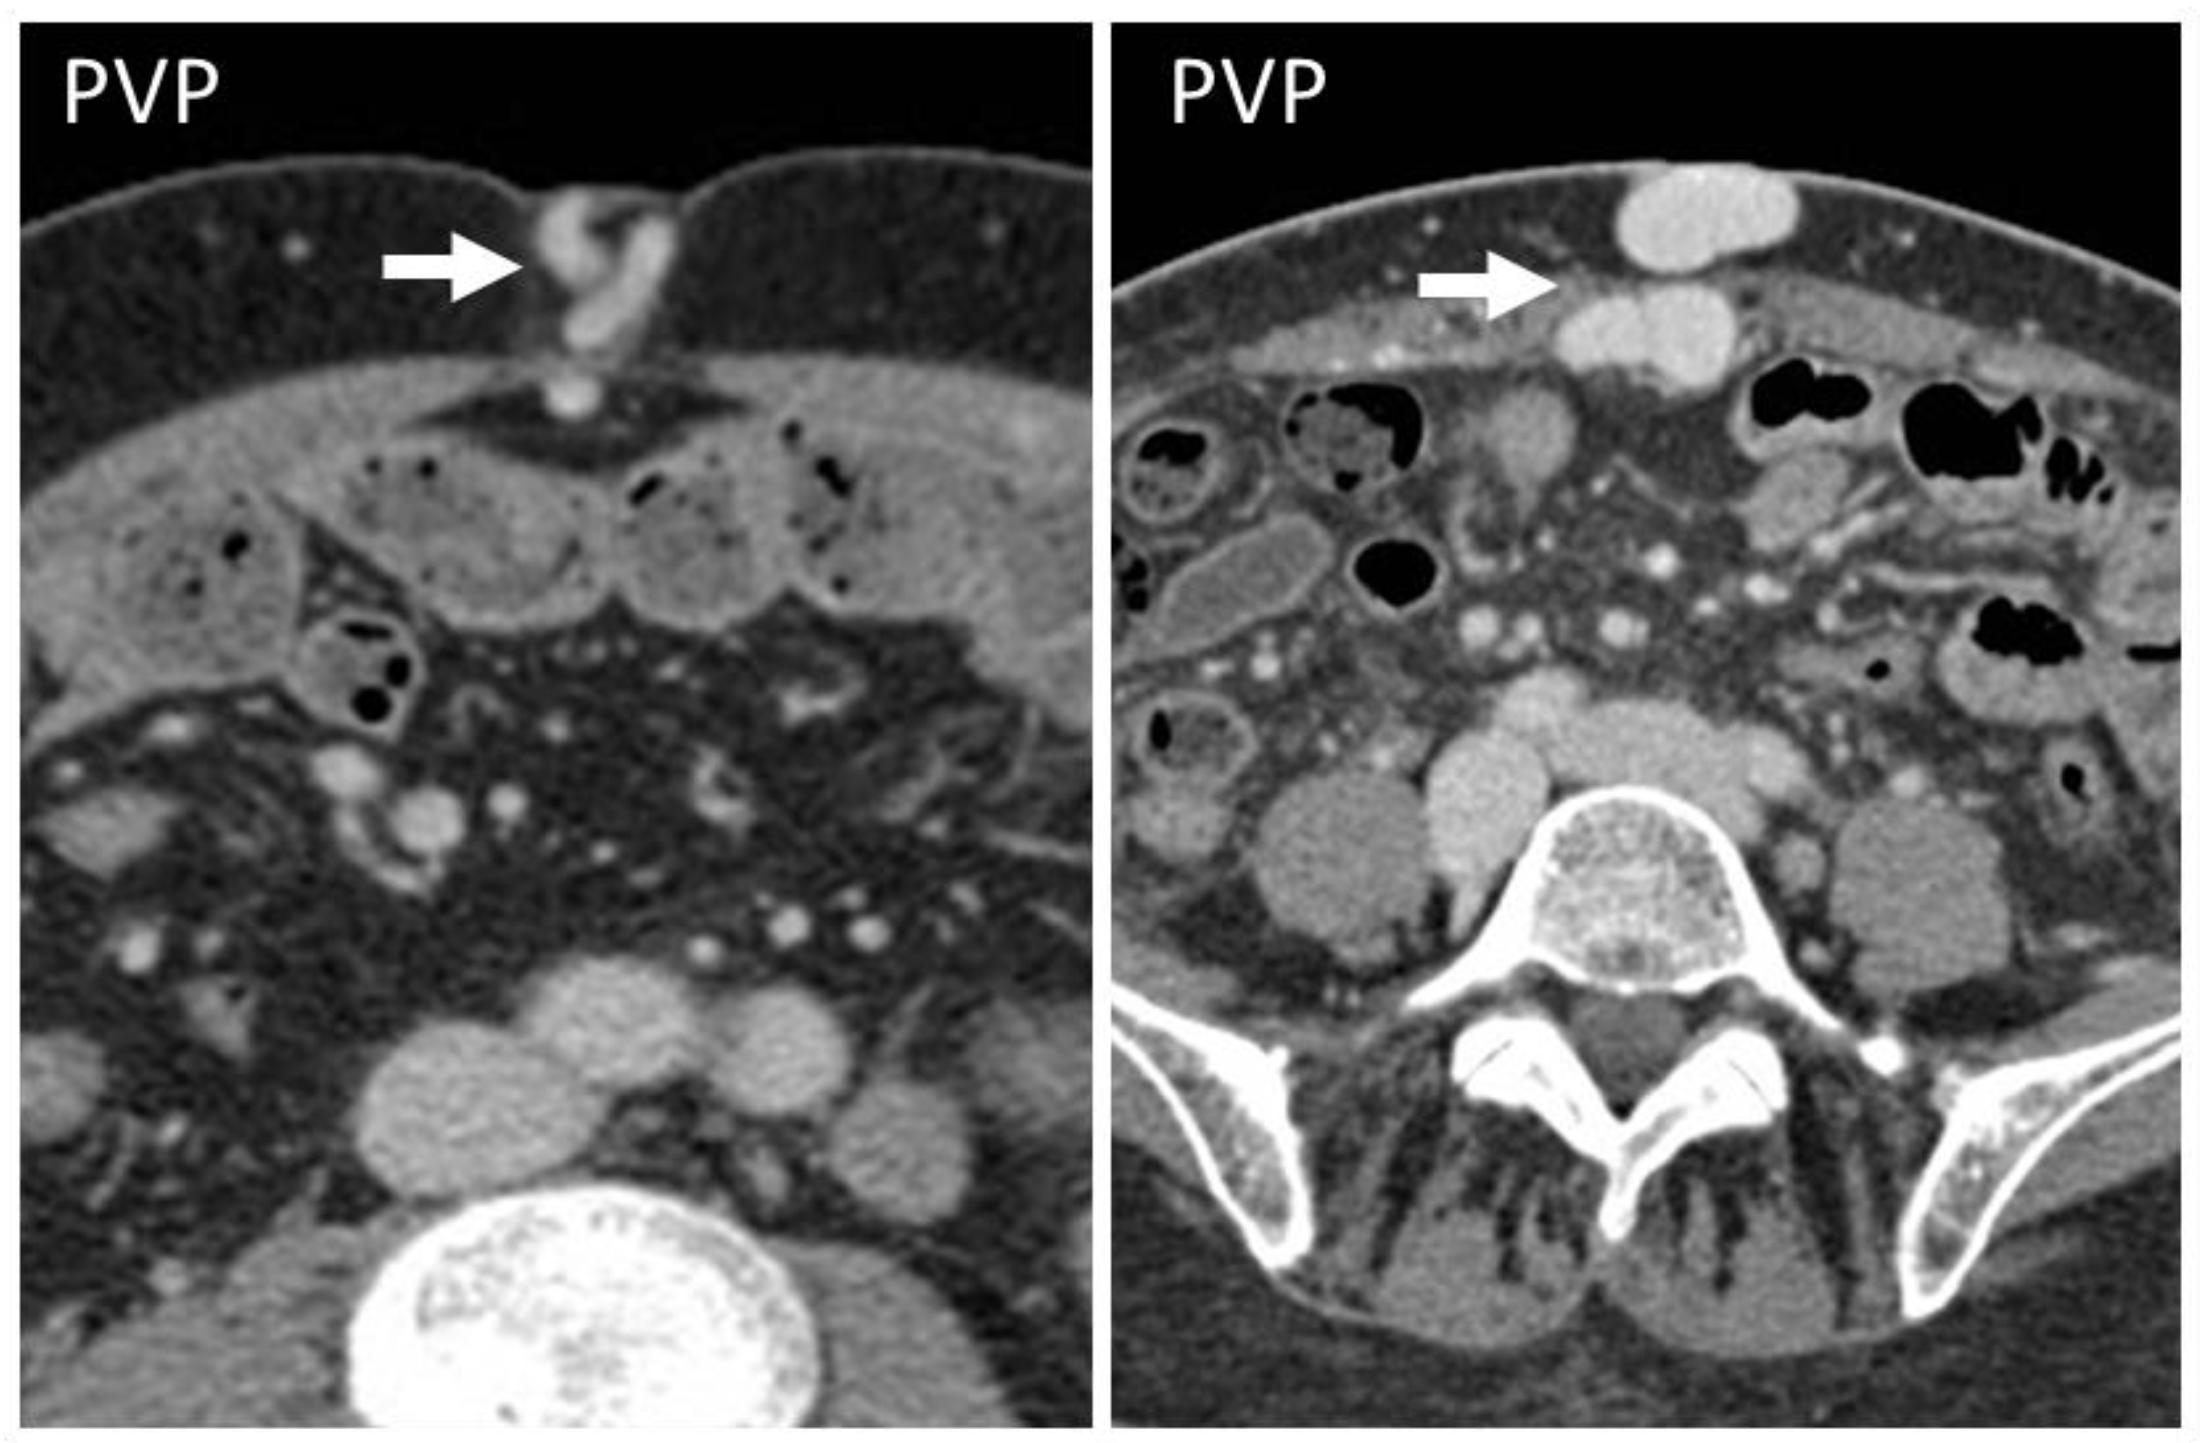

5.5. Splenosis